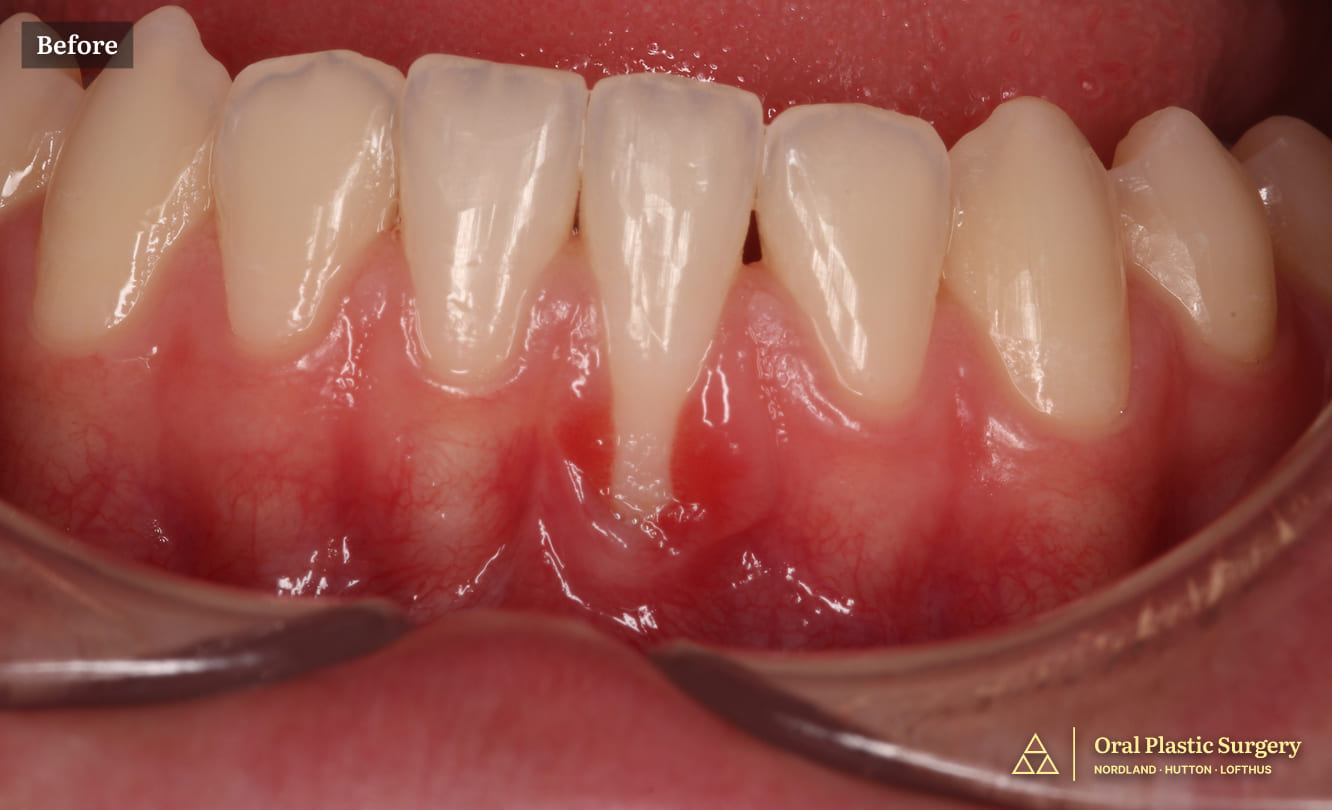

Niko had longstanding gum recession with severe root exposure affecting multiple teeth. Over time, the exposed root surfaces began to break down due to the softness of the root structure compared to enamel and constant exposure to the harsh oral environment.

Brown areas on the exposed roots reflected demineralization of the root dentin, and the surrounding gum tissue became inflamed, irritated, and prone to bleeding.

Maintaining oral hygiene was uncomfortable, and routine hygiene appointments became increasingly difficult.

Niko also felt self-conscious about his smile. He noticed the brown exposed roots in the mirror and did not feel confident smiling or speaking.

The before image shows recession affecting multiple teeth in the left quadrant, with visible root exposure The after image shows post-operative outcome demonstrating successful root coverage and increased width of keratinized tissue